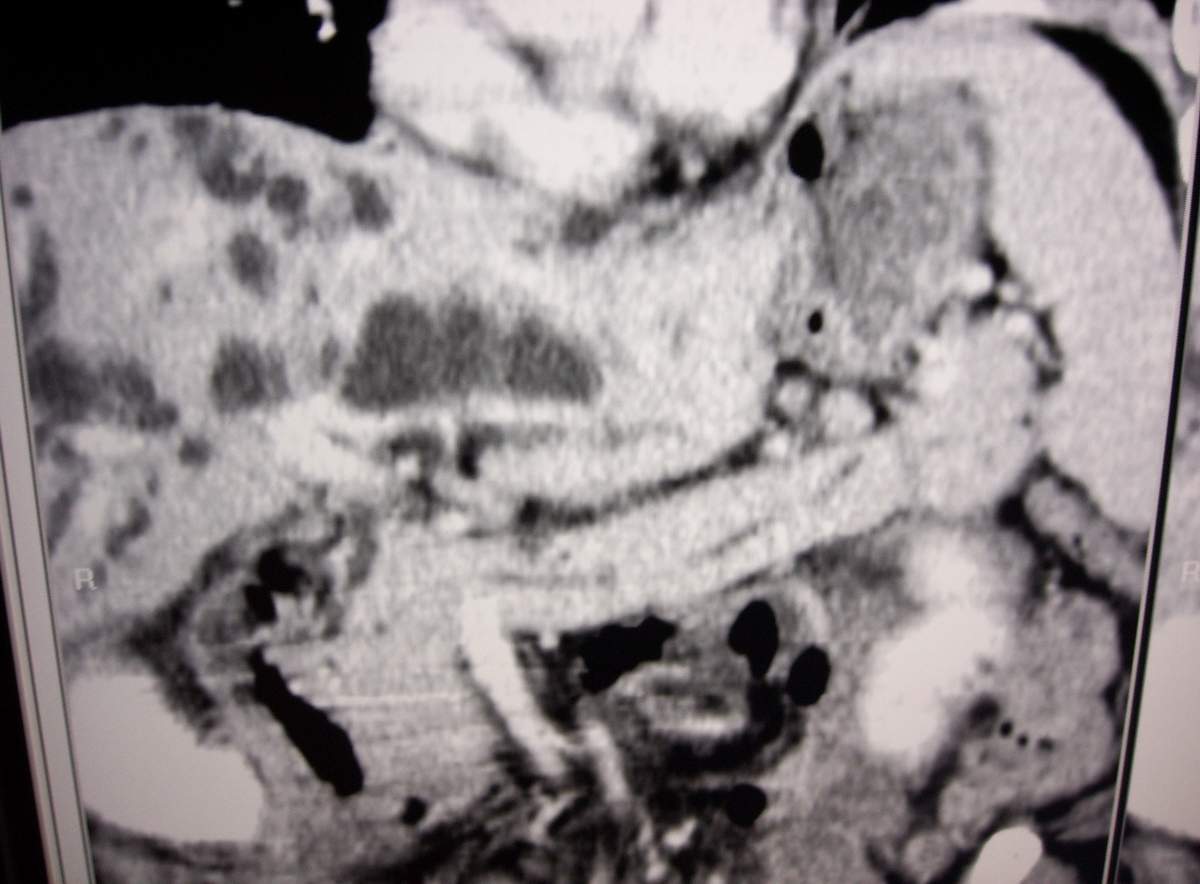

男,77岁,病史不详。

肝内外胆管明显扩张,肝门区见软组织密度肿块,胆囊壁增厚,胆囊扩大。胰头不大。考虑:肝门区胆管细胞癌。

肝内胆管普遍扩张,呈串珠状改变,走行不规则,且右叶胆管周围肝实质密度呈条片状减低,未见占位性病变,外周胆管及胰管扩张不及肝内胆管.胰腺钩突形态正常,胰十二指肠区域未见明显结节及肿块,初步考虑慢性胆管炎可能性大.请结合临床病史.另外用宽窗看一下吉氏筋膜有无增厚.

1 肝内外胆管扩张,肝内明显,胰管扩张,胰头明显增大,符合胰头癌双管征。2 胆囊壁略增厚,胆囊内可见高密度结石影,胆囊炎、胆结石3 左肾囊肿